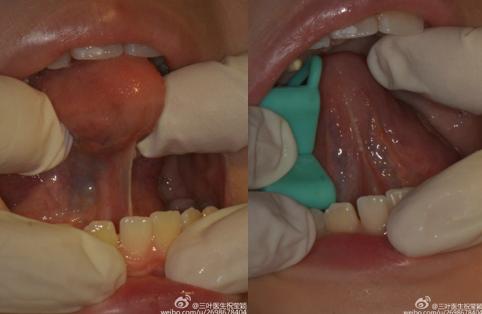

舌系带俗称“舌筋”,

是口底和舌尖相连的一条粘膜皱襞。

如果舌系带短

可能出现如下症状:

5、伸舌时舌尖呈“W”型

6、舌尖不能上抬至上腭

目前有多种舌系带延长的手术方式,比较先进的是激光无痛手术:安全,无痛,迅速(手术只需几分钟),几乎不用缝合,愈合速度较快,创面恢复较好。